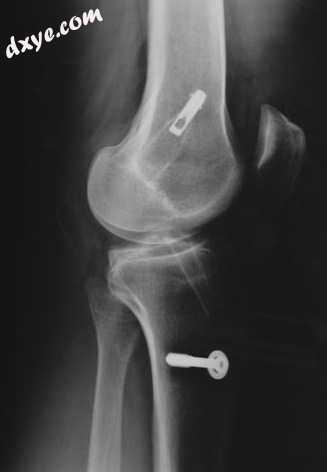

将移植物插入穿过胫骨(胫骨)和大腿骨(股骨)的隧道中。然后将移植物拉过隧道并用螺钉固定。此X射线中的两个明亮物体是大腿骨(上方)和胫骨(下方)的螺钉。